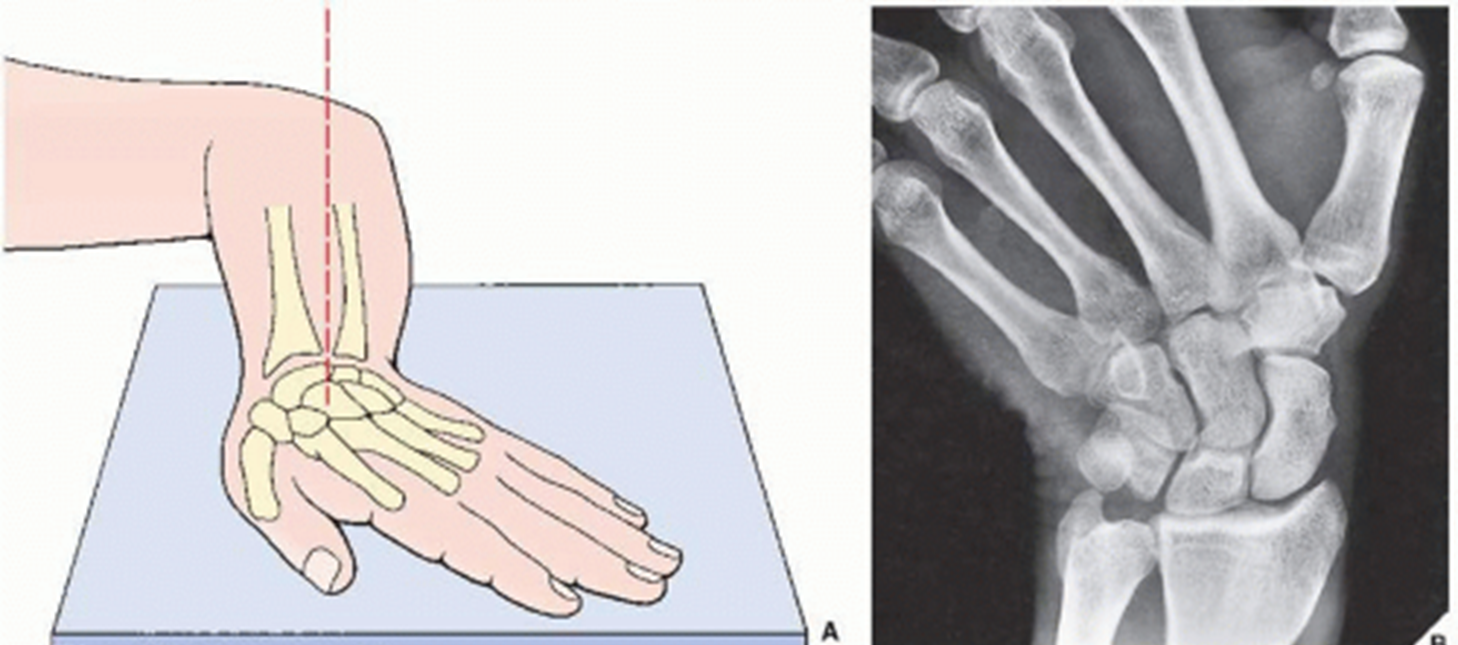

What view is this

radial deviation

what does the radial deviation show best

lunate

triquetrum

hamate

pisiform